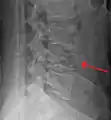

A burst fracture of L4 as seen on plane X ray

A burst fracture of L4 as seen one plane X ray